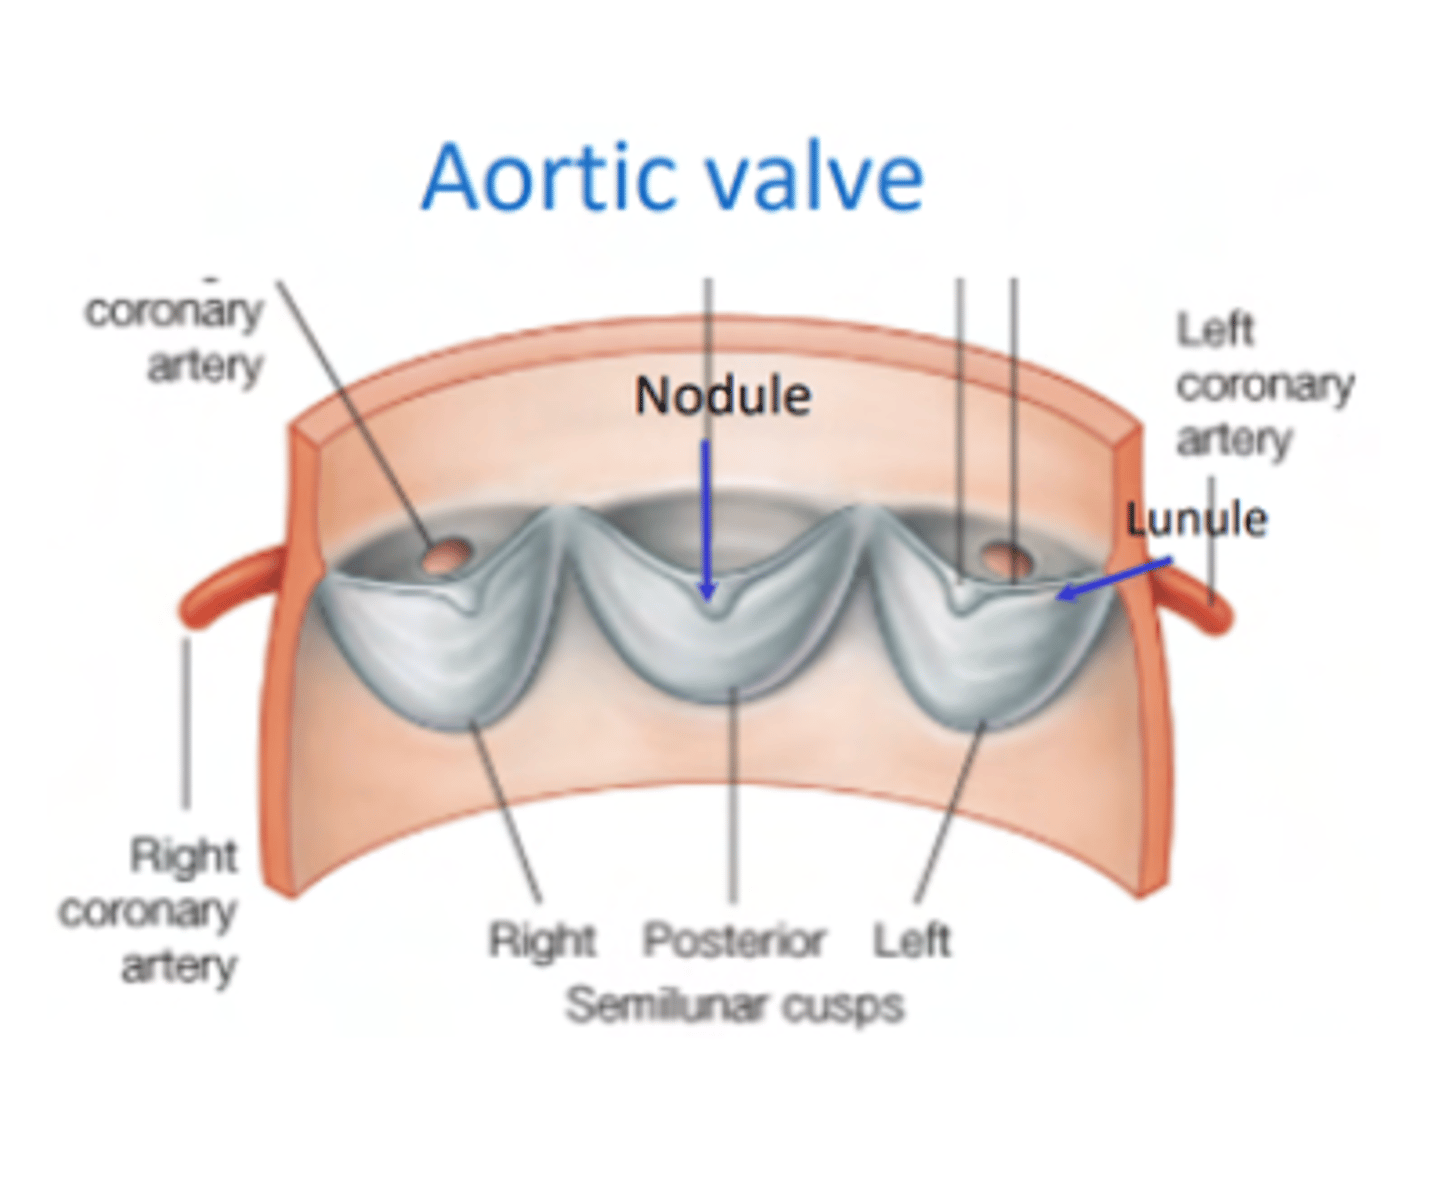

What is the valve to prevents reflux in the aorta?

Aortic valve

What are the 3 parts of the aortic valve?

3 semilunar cusps

posterior

right

left

POSITION IS DIFFERENT THAT IN THE PULMONARY (posterior vs anterior)

What is the structure of the cusps of the aortic valve?

. Nodules

. Lunules

. Small holes for the coronary arteries

MAIN DIFFERENCE WITH PULMONARY VALVES ARE THE SMALL HOLES FOR THE CORONARY ARTERIES.

What is the 1st branch of the aorta?

The small holes in the aortic valve cusps to irrigate the coronary arteries.